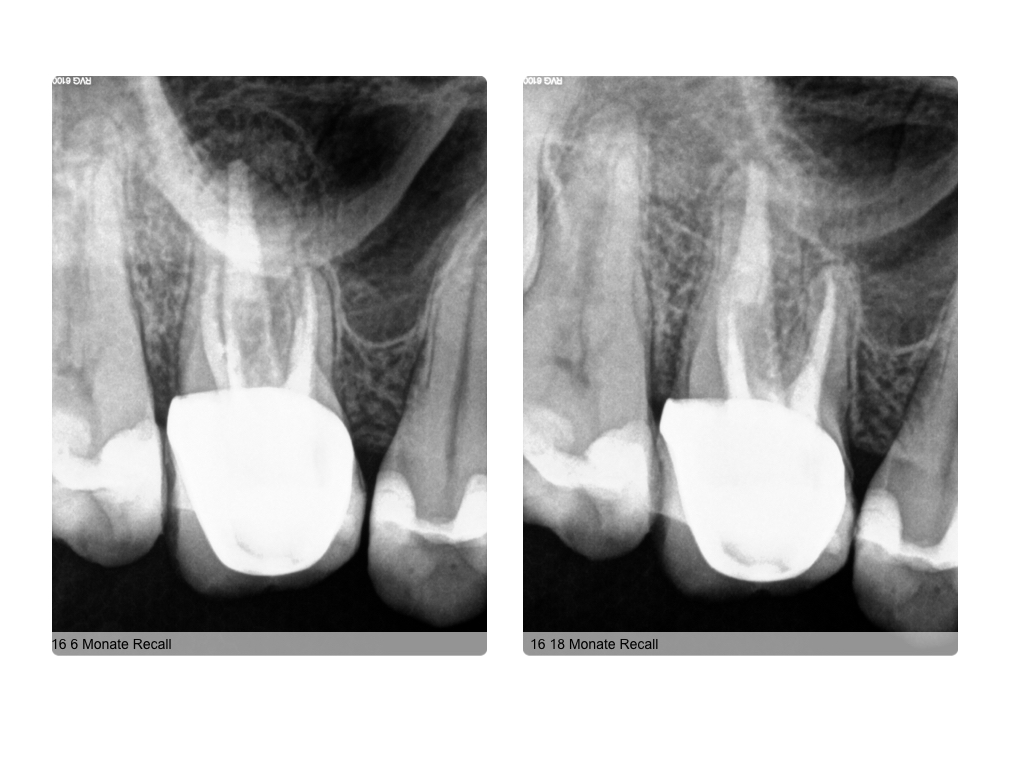

Healing?